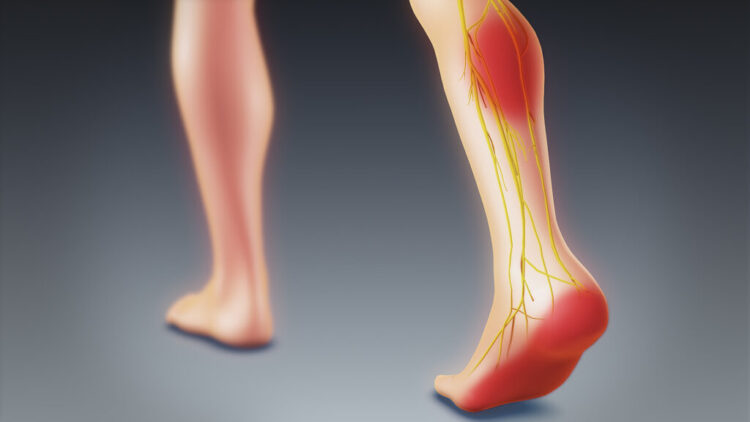

L4 RAPOSA’s feet are not only swift for gaming moves but also incredibly aesthetic! From her well-aligned toes to the arches that provide support and flexibility, every part of her foot is a work of art. The smooth soles of her feet effortlessly glide across the ground, showcasing grace in each step. Anchored by strong and elegant ankles, L4 RAPOSA’s feet lead up to toned legs that add power to her dance and gaming skills. Her heels provide stability while the well-defined arches offer both strength and poise. Overall, her entire lower extremities embody both beauty and function .